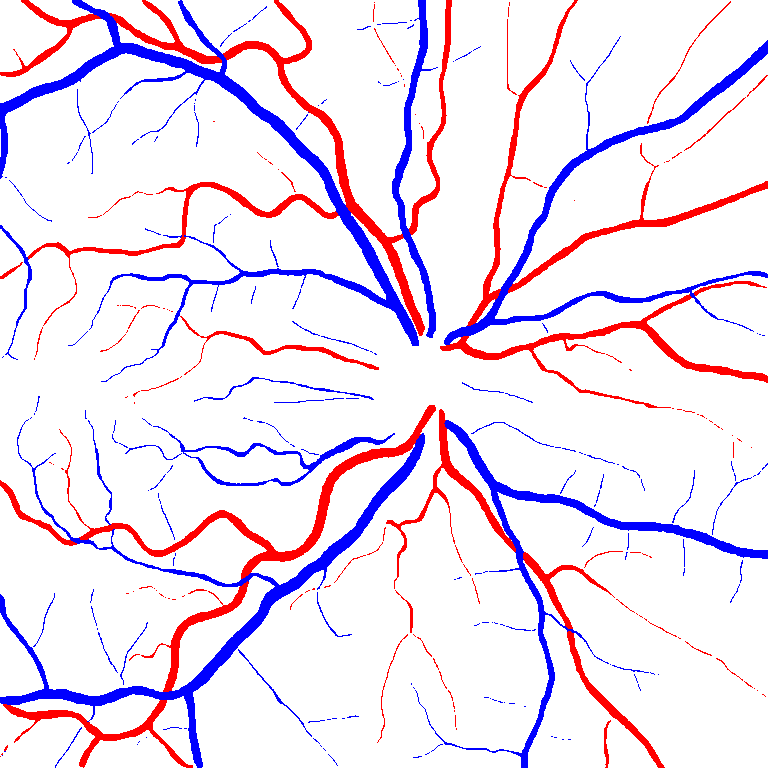

VI-A Retinal Artery and Vein Segmentation

As reported in Table IV, we compared the SegRAVIR model against competing deep learning-based segmentation approaches on the RAVIR dataset. Evidently, SegRAVIR outperforms these methods as judged by all metrics for artery and vein classes with a healthy margin. In terms of Dice score, SegRAVIR outperforms CE-NET, IterNet and AG-Net by , and for artery segmentation and by , and for vein segmentation, respectively. Fig. 4 presents a qualitative comparison of the semantic segmentation outputs of SegRAVIR, CE-Net, and U-Net. Specifically, SegRAVIR yields more accurate vessel topology (i.e., thickness and orientation) segmentation with higher pixel-wise classification accuracy.